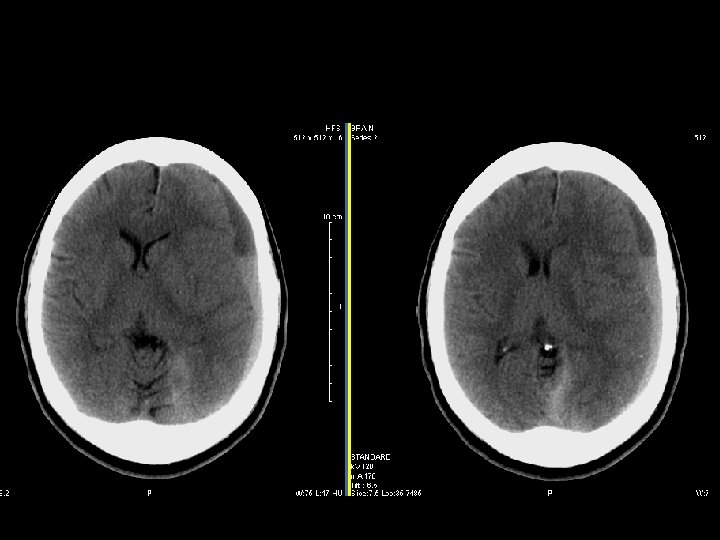

Intraparenchymal hematoma n Kumpulan darah fokal yang tersering timbul dari shear-strain injury pada pembuluh darah intraparenkim n Umumnya berlokasi pd frontotemporal white matter atau basal ganglia n Hematoma di dalam parenkim otak yang normal n DDx: DAI, hemorrhagic contusion

Perdarahan Intraventricular n Paling sering akibat ruptur pembuluh darah subependymal n Dapat timbul akibat refluks dari SAH atau perluasan dari perdarahan intraserebral n Lihat adanya blood-cerebrospinal fluid level di occipital horns